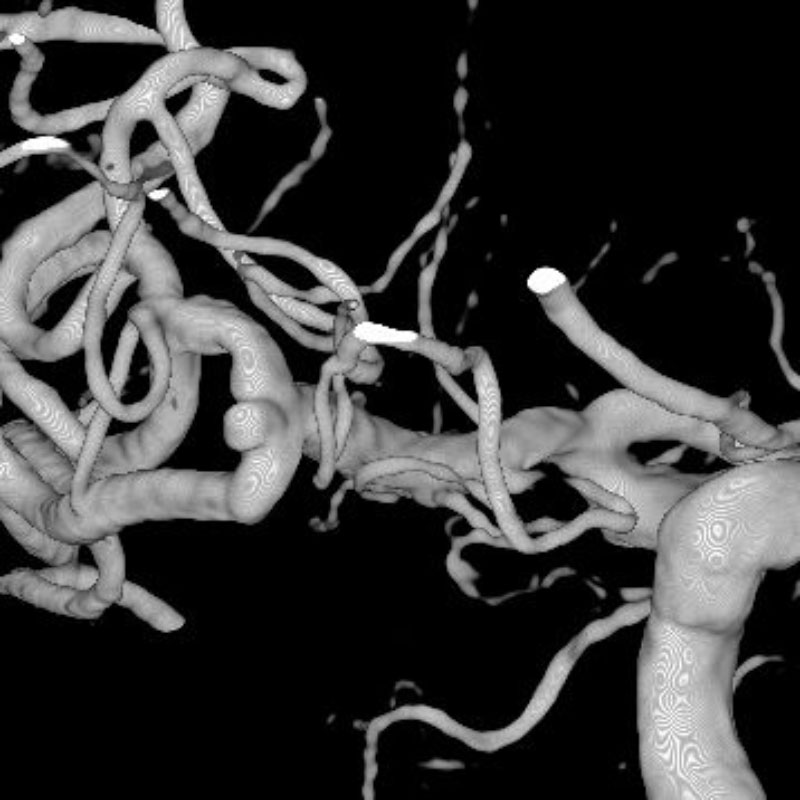

脳動静脈奇形

血管塞栓術

松田/濵田/元永